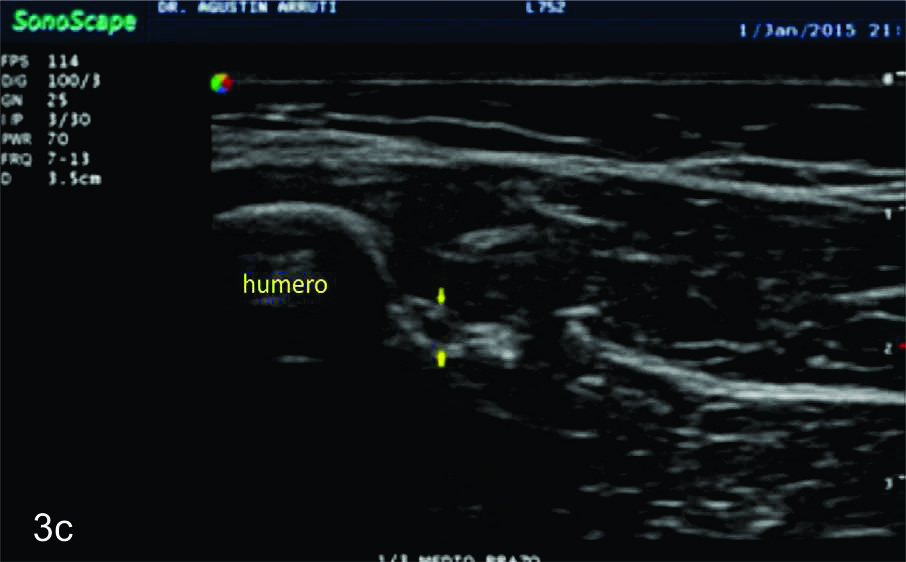

Figura 14 e, f, g y h

Lesión traumática del plexo braquial luego de accidente en moto.

EyF-Cortes comparativos a nivel de cara anterior de brazo derecho o afectado (E) y brazo izquierdo o sano (F), en donde se identifica la clara asimetría en el volumen y ecogenicidad de los planos musculares (flechas azules) en relación a cambios por atrofia. H- diáfisis humeral. GyH- Cortes comparativos a nivel de la cara anterior del antebrazo derecho o afectado (H) e izquierdo o sano (G), demuestra hallazgos similares. R- Diafisis radio, C- Diafisis cubito.